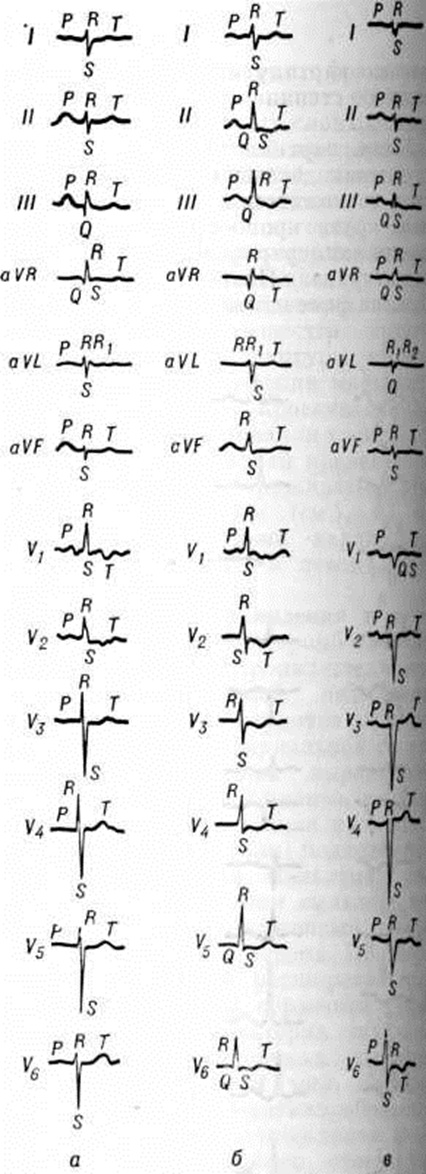

Клинические проявления и течение. Острое Лёгочное сердце при тромбоэмболии лёгочных артерий проявляется быстро прогрессирующей недостаточностью правого желудочка на фоне явной лёгочной артериальной гипертензии. Характерны выраженная одышка, диффузный цианоз, набухание шейных вен, видимая пульсация грудной стенки и (или) подложечной области. Глубокая пальпация под мечевидным отростком выявляет нередко упругий напряжённый толчок правого желудочка сердца. При перкуссии выявляется расширение границ относительной сердечной тупости вправо. Характерна тахикардия с числом сердечных сокращений более 100 в 1 минуту. Нередко определяется маятникообразный ритм звучания сердечных тонов. Второй тон сердца усилен, отмечается резкий его акцент над лёгочной артерией. артериальное давление, как правило, снижено, возможен коллапс. Печень часто выступает из-под рёберной дуги, край её нередко болезнен; иногда жалоба на боль в правом подреберье (в связи с острым растяжением капсулы печени) становится одной из доминирующих; возможны тошнота и рвота. На ЭКГ определяются признаки перегрузки правого предсердия (высокие заострённые — «лёгочные» зубцы Р во II и III стандартных отведениях, преобладание положительной фазы зубца Р в отведении V1) и правого желудочка, что проявляется отклонением электрической оси сердца вправо (более заметным при сравнении с ЭКГ, зарегистрированными до заболевания), появлением или увеличением зубцов R или R в однополюсных отведениях от правой руки и правых грудных, углублением зубцов S в левых грудных отведениях и смещением вниз сегмента S — Т в отведениях II, III, aVP. Изменения ЭКГ при остром Лёгочное сердце вследствие тромбоэмболии лёгочной артерии (в частности, синдром SIQIII) могут имитировать картину инфаркта миокарда задней стенки левого желудочка (рисунок 2).

Начальные изменения ЭКГ при хронический заболеваниях лёгких чаще всего отражают ротационные сдвиги: 1) вертикальная или полувертикальная позиция сердца (в ряде случаев с отклонением электрической оси сердца вправо); 2) сдвиг переходной зоны влево за счёт поворота сердца по часовой стрелке вокруг продольной оси; 3) отклонение верхушки назад в связи с поворотом вокруг поперечной оси сердца. Диффузные изменения миокарда проявляются прежде всего уменьшением амплитуды зубцов комплекса QRS. Прогрессирование лёгочной артериальной гипертензии отражается на ЭКГ изменением предсердного компонента по типу «лёгочного» зубца Р (pulmonale). При различных формах гипертрофии правого желудочка встречаются разные типы кривых ЭКГ; в зависимости от преобладания зубца R в правых грудных отведениях или зубца S в левых грудных говорят о R-типе или S-типе, а при комбинации этих признаков — о Rv1— Sv5-типах кривой (рисунок 3). Для R-типа кривой ЭКГ характерен зубец Rv1 без выраженного зубца Sv5 (результирующий вектор отклоняется при этом вправо и вперёд), для S-типа — малый зубец Rv1 и глубокий зубец Sv5 (результирующий вектор отклоняется вправо и назад). Промежуточные формы кривой ЭКГ с несколько увеличенным зубцом Rv1 и довольно выраженным зубцом Sv5 дают отклонение результирующего вектора только вправо.

Электрокардиографической диагностике Лёгочное сердце способствует тщательная оценка прямых и косвенных (обусловленных преимущественно позиционными изменениями сердца) признаков гипертрофии правого желудочка. Выделяют следующие прямые признаки гипертрофии правого желудочка: ![]() 3) Rv1 + Sv5 ≥ 10,5 миллиметров; 4) время внутреннего отклонения в отведении V1 — 0,03—0,05 секунд; 5) форма QRv1; 6) Rv1 > 10 миллиметров при неполной блокаде правой ножки; 7) Rv1 > 15 миллиметров при полной блокаде правой ножки; 8) признаки систолической перегрузки правого желудочка в отведениях V1,2. Наряду с этим различают 12 косвенных признаков гипертрофии правого желудочка:

3) Rv1 + Sv5 ≥ 10,5 миллиметров; 4) время внутреннего отклонения в отведении V1 — 0,03—0,05 секунд; 5) форма QRv1; 6) Rv1 > 10 миллиметров при неполной блокаде правой ножки; 7) Rv1 > 15 миллиметров при полной блокаде правой ножки; 8) признаки систолической перегрузки правого желудочка в отведениях V1,2. Наряду с этим различают 12 косвенных признаков гипертрофии правого желудочка: ![]() ; Rv1 миллиметров при неполной блокаде правой ножки; 5) Rv1 < 15 миллиметров при полной блокаде правой ножки; 6) индекс

; Rv1 миллиметров при неполной блокаде правой ножки; 5) Rv1 < 15 миллиметров при полной блокаде правой ножки; 6) индекс ![]() - 7) отрицательные зубцы Tv1-3; 8) < 2 миллиметров; 9) Р pulmonale (высокие, часто остроконечной формы зубцы) во II и III отведениях; 10) электрическая ось ЭКГ по стандартным отведениям > 110°; 11) тип ЭКГ SI — SIII; 12) R/QaVR > 1. Сочетание двух или более прямых признаков делает диагноз гипертрофии правого желудочка несомненным. При наличии одного прямого и одного косвенного или двух непрямых признаков гипертрофия правого желудочка представляется вероятной. Если же имеется только один прямой или один косвенный признак, то диагноз гипертрофии правого желудочка остаётся сомнительным.

- 7) отрицательные зубцы Tv1-3; 8) < 2 миллиметров; 9) Р pulmonale (высокие, часто остроконечной формы зубцы) во II и III отведениях; 10) электрическая ось ЭКГ по стандартным отведениям > 110°; 11) тип ЭКГ SI — SIII; 12) R/QaVR > 1. Сочетание двух или более прямых признаков делает диагноз гипертрофии правого желудочка несомненным. При наличии одного прямого и одного косвенного или двух непрямых признаков гипертрофия правого желудочка представляется вероятной. Если же имеется только один прямой или один косвенный признак, то диагноз гипертрофии правого желудочка остаётся сомнительным.

Для электрокардиографической диагностики лёгочной артериальной гипертензии при хронический заболеваниях органов дыхания Бернар (R. Bernard) с соавторами (1974) предложили следующие критерии: 1) отрицательные зубцы Tv1-3; 2) угол электрической оси QRS > 90°; 3) отношение 100/R (R + S) в отведении V5 < 50; амплитуда зубца РII 2 миллиметров; отношение 100 Р/ (R + S) во II отведении > 20; 6) отношение 100R/(R + Q) в отведении aVR >> 50; 7) отношение 100R/(R + S) в отведении V1 > 50. При наличии двух из указанных патологический признаков существует большая вероятность того, что давление в лёгочной артерии достигает 20 миллиметров ртутного столба или превышает эту величину; выявление трёх признаков позволяет говорить о лёгочной гипертензии почти с уверенностью.